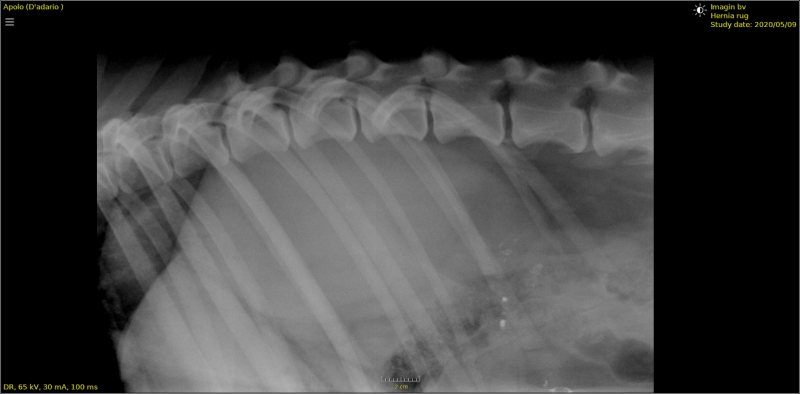

Twee gevallen van een ernstige cervicale discus hernia.

Engelse bulldog van 5 jaar met parese achterhand.

Discus hernia op overgang L6-L7 en lumbosacraal.